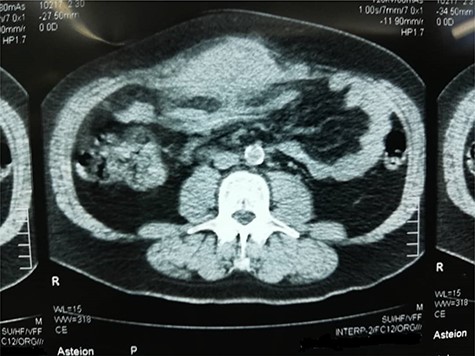

Computed tomography (CT) scan depicted a solid irregular density 15 × 11.5 × 6 cm sized, occupying bilaterally musculus rectus in the umbilical area. The lesion was projecting through anterior abdominal wall lipoid tissue and posterior mesenteric lipoid tissue. The mass had a heterogeneous characteristic; 2 cm of the bowel was infiltrated within the mass. It also showed no enlargement of lymph nodes or other organs (Fig. 2).

CT scan of the tumor as it shows infiltration to adjacent structures and attachment to the anterior abdominal wall.